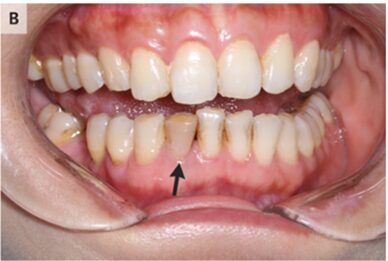

口腔内検査では下顎の右側切歯の変色があった。

歯原性皮膚瘻は顎や顔に「えくぼ」「小結節」「膿疱」として現れる。